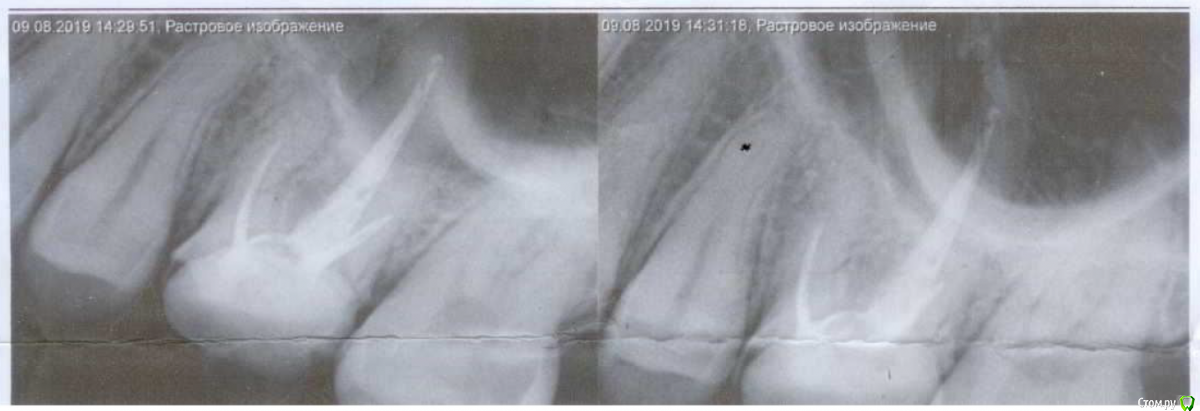

Где-то 3 недели назад эта шестёрка начала разрушаться и в какой-то момент откололся сразу большой кусок зуба. В результате осталось где-то 50% поверхности зуба. Какое-то время из-за этого болела десна, но это прошло довольно быстро. Я пошёл к стоматологам. Был у нескольких, на всякий случай. Сделал снимки (в том числе и 3D, но его я, к сожалению, пока приложить не могу, ибо оставил его дома на диске, выложу как приеду, если будет нужно, 2D снимки прикрепил). По снимкам все врачи нашли что-то плохое под зубом около пазухи (но не доходя до неё, пока, но говорят, что она довольно близко). Говорили разное: либо киста, либо воспаление.

Прикреплено:

2) Одиночный снимок - сделан месяц назад;

3) Одиночный снимок - сделан 8 дней назад, но он менее чёткий.